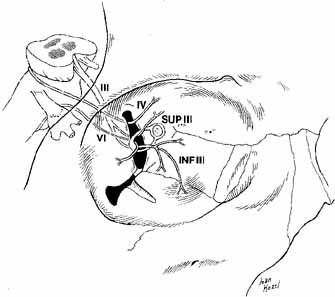

superior orbital fissure is a transverse notch between the greater

and lesser wings of the sphenoid bone that descends medially (see Fig. 1). Although the shape of the superior orbital fissure is variable, the

superior portion is usually narrower where the lacrimal, frontal, and

trochlear nerves pass (Fig. 6). The middle meningeal artery anastomosis with the ophthalmic artery

structures passing through the superior orbital fissure within the annulus

of Zinn include the superior and inferior divisions of the third

cranial nerve, the sixth cranial nerve, and the nasociliary branch of

the ophthalmic trigeminal nerve (Fig. 6). Fig. 6 Orbital apex with nerves coursing through foramina. (LN, lacrimal nerve; NCN, nasociliary nerve; FN, frontal nerve; VI, abducens nerve; IV, trochlear nerve; INF III, inferior division of cranial nerve III; SOV, superior ophthalmic vein; II, cranial nerve II; SUP III, superior division of cranial nerve III; IOV, inferior ophthalmic vein; ZN, zygomatic nerve; V2, V2 nerve; SGB, sphenopalatine ganglion branches) Fig. 6 Orbital apex with nerves coursing through foramina. (LN, lacrimal nerve; NCN, nasociliary nerve; FN, frontal nerve; VI, abducens nerve; IV, trochlear nerve; INF III, inferior division of cranial nerve III; SOV, superior ophthalmic vein; II, cranial nerve II; SUP III, superior division of cranial nerve III; IOV, inferior ophthalmic vein; ZN, zygomatic nerve; V2, V2 nerve; SGB, sphenopalatine ganglion branches)

rectus (90%) or through it (10%) (Fig. 18).  Fig. 18 Nerves to the extraocular muscles. The superior and inferior divisions

of the oculomotor nerve are separated by the nasociliary nerve within

the superior orbital fissure. The superior division supplies the superior

rectus and the levator palpebrae superioris muscles. The inferior

division supplies the inferior and the medial rectus muscles and the inferior

oblique muscle. The trochlear nerve supplies the superior oblique

muscle, whereas the abducens nerve innervates the lateral rectus muscle. (III, cranial nerve III; IV, cranial nerve IV; VI, cranial nerve VI; SUPIII, superior division of cranial nerve III; INFIII, inferior division of cranial nerve III) Fig. 18 Nerves to the extraocular muscles. The superior and inferior divisions

of the oculomotor nerve are separated by the nasociliary nerve within

the superior orbital fissure. The superior division supplies the superior

rectus and the levator palpebrae superioris muscles. The inferior

division supplies the inferior and the medial rectus muscles and the inferior

oblique muscle. The trochlear nerve supplies the superior oblique

muscle, whereas the abducens nerve innervates the lateral rectus muscle. (III, cranial nerve III; IV, cranial nerve IV; VI, cranial nerve VI; SUPIII, superior division of cranial nerve III; INFIII, inferior division of cranial nerve III)